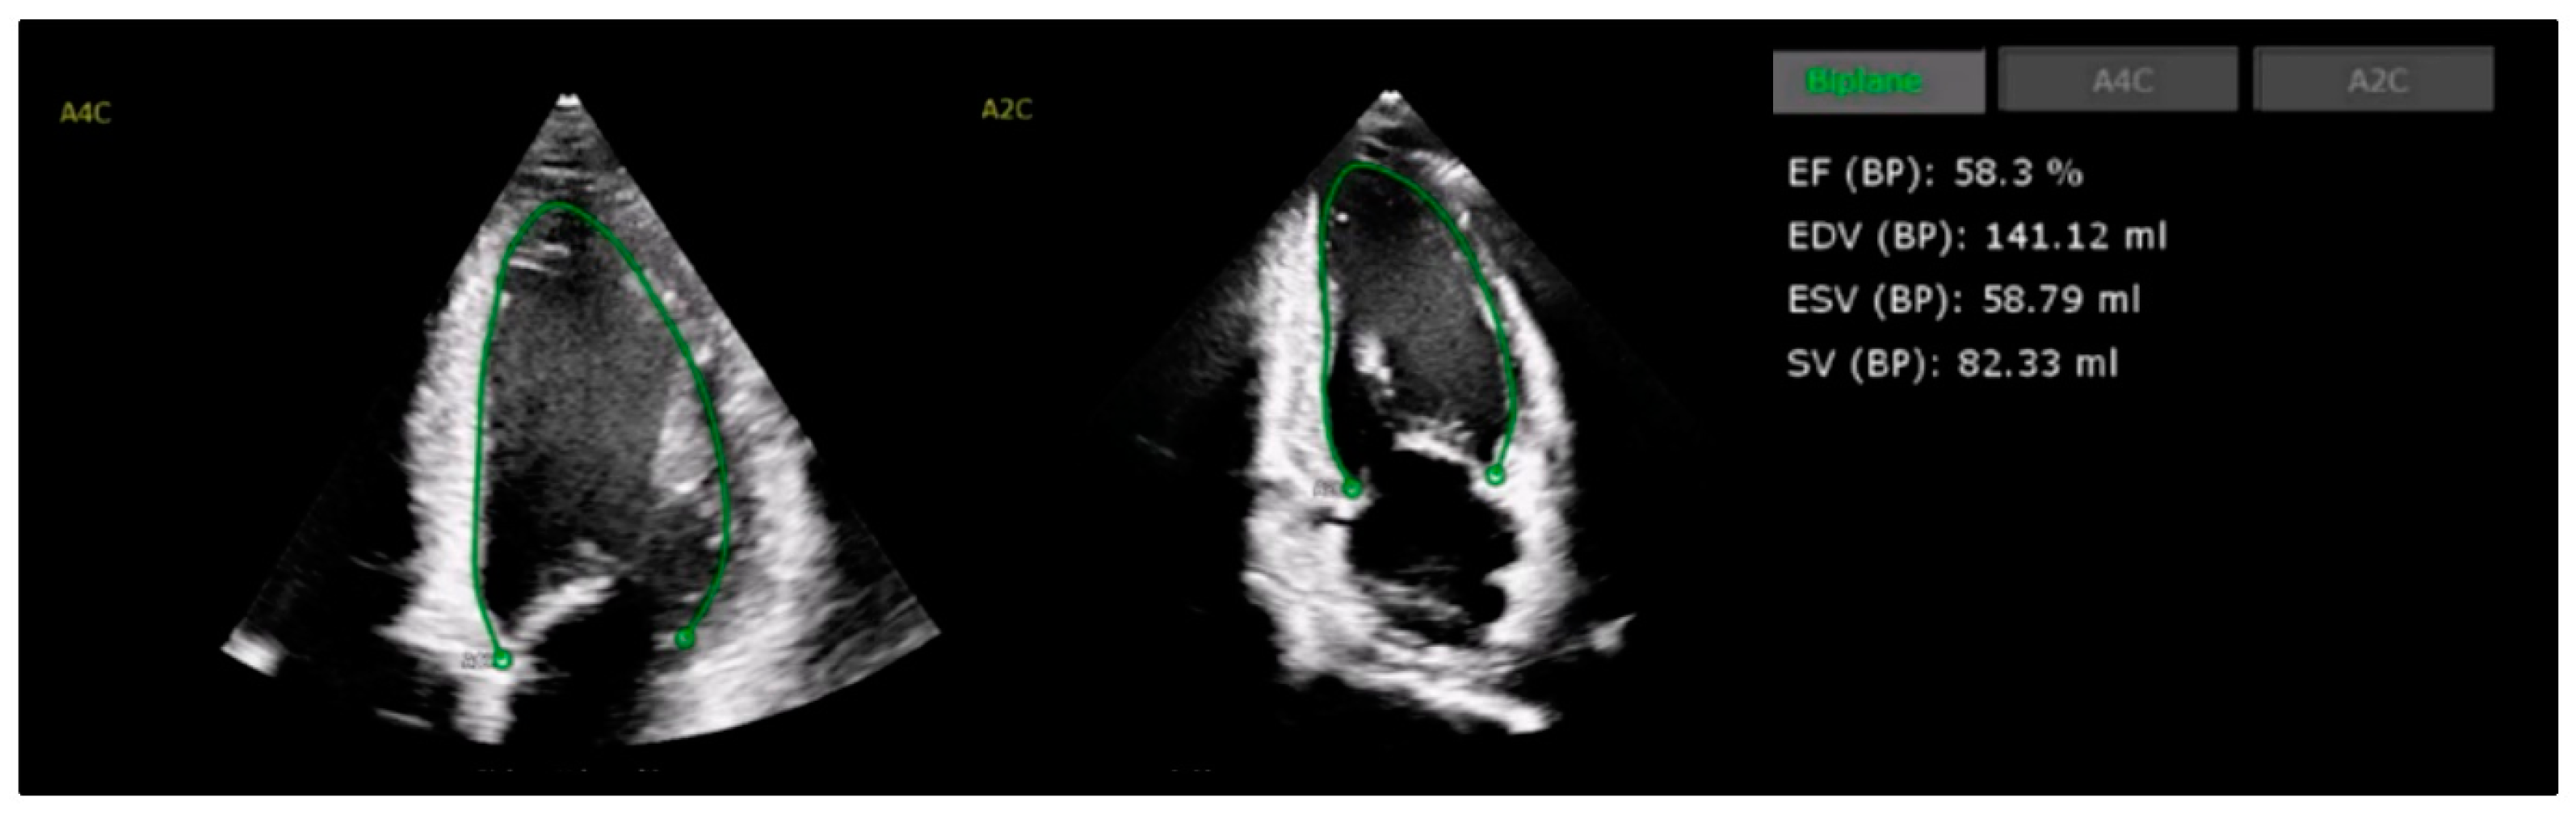

4.1. Left Ventricular Systolic Function

- Jiang, J.; Liu, B.; Li, Y.W.; Hothi, S.S. Clinical service evaluation of the feasibility and reproducibility of novel artificial intelligence based-echocardiographic quantification of global longitudinal strain and left ventricular ejection fraction in trastuzumab-treated patients. Front. Cardiovasc. Med. 2023, 10, 1250311. [Google Scholar] [CrossRef]